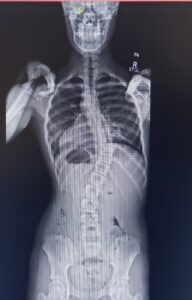

In March of 2018, while having a dress altered, my seamstress noticed that my shoulders were uneven. Shortly after that, my parents took me to a free screening clinic from Shriners Children’s where I had x-rays done on my back. Doctors found three curves – one in my neck and two in my spine. I was diagnosed with Adolescent Idiopathic Scoliosis and immediately was sent to Shriners Children’s in a larger city, about 7 hours away from where I live. Then, doctors fit me for my first back brace which I had to wear 20 hours every day to hopefully stop the progression of the curvature of my spine. They also gave me extensive physical therapy exercises (scoliosis specific exercises – SSE – or the Schroth method) to do at home each day. At first, wearing the brace was NOT fun! It is very restrictive, and as someone who just wants to move, dance and do acrobatics all the time, it was pretty difficult to get used to. I was also kind of nervous that it would look weird with my clothes.

I wore my brace very diligently for one month and had to go back to the clinic for a follow-up appointment so that my doctors could make sure everything was working. In just one month’s time, my spine had progressed 10 degrees! My doctor told me that it was one of the fastest-progressing case of scoliosis he had ever seen. At that point, everyone was confused and worried. I had to get a full-spine MRI to rule out any other underlying causes that may have explained this big jump. Luckily, everything showed up normal on the MRI. I was sent home with some modified physical therapy exercises for my curve and was being closely monitored.

I didn’t experience another jump like that for almost two years. Every day I wore my brace 20 hours (the time off was spent dancing) to hopefully avoid progression. I learned how to deal with my brace and my spine was staying stable. I realized what I was trying to steer away from – major spine surgery – and that almost scared me into wearing the brace. I didn’t want surgery, because all I wanted to do was keep dancing and maintain flexibility in order to do so. I had no pain with my scoliosis at all until shortly after my February 2020 doctor’s appointment. I was supposed to go to the clinic in May 2020 for a regular visit/checkup, but by then, the Coronavirus pandemic was a major problem so we postponed the appointment. My spine had been stable for two years, I hadn’t changed anything – I was still doing PT and bracing – and so we figured it would be okay to wait another month. But when we went to the appointment rescheduled for the end of June, we realized that my spine curvature had jumped yet again. No wonder my back had started hurting; another 10 degree jump meant my curve measured 45 degrees.